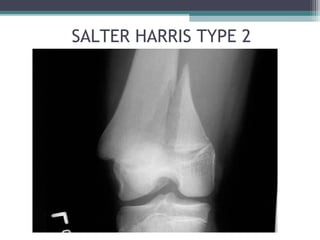

SALTER HARRIS TYPE 2

▫ TYPE 2: ABOVE FRACTURE VEERING OFF INTO

METAPHYSIS TO INCLUDE A TRIANGULAR CHIP OF BONE

• COMMONEST IS TYPE 2 (75% OF PHYSEAL INJURIES)